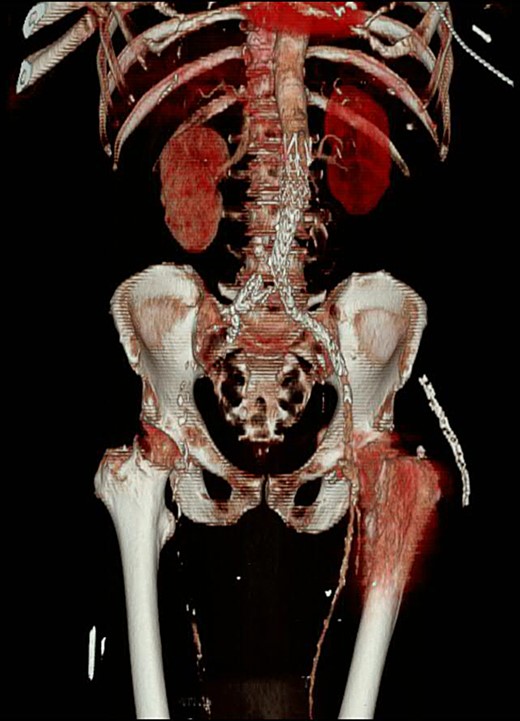

A 74-year-old male was admitted with an intracapsular fractured left neck of femur (Fig. 1). According to the NICE guidelines, he received a cemented THR (Fig. 2) via the posterior approach in the lateral decubitus position. Five weeks prior, he had an EVAR for a leaking AAA. Due to a calcified, narrow right common iliac artery (CIA), the EVAR consisted of a left aortouniiliac endograft with coil embolization of the right CIA and a femoro-femoral crossover graft (Figs 3 and 4).

CT angiogram with three-dimensional reconstruction revealing a filling defect to the right lower limb with an absence of collateral circulation.